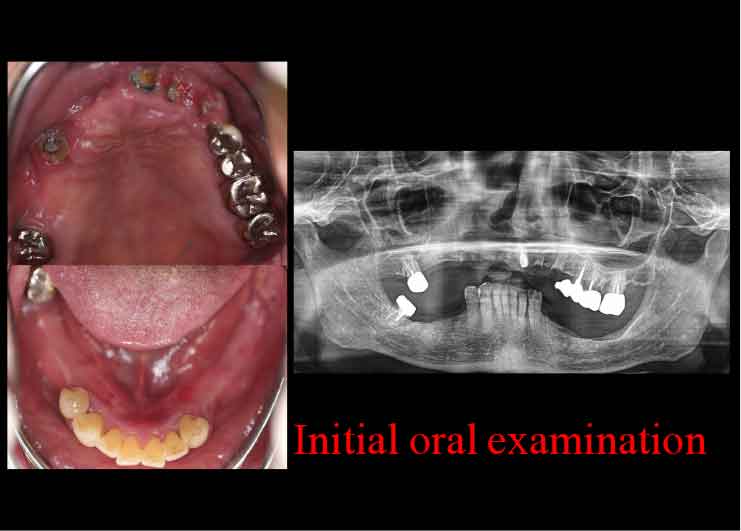

Case2. 68歳男性

下歯槽神経近くにインプラントを埋入したケース。

歯を失った下あごの骨が大きく吸収し、下歯槽神経の出入り口であるオトガイ孔が表面に近い部分に出てきています。そこで、X-ガイド使用により、下歯槽神経を避けた手術を行いました。

CTスキャンを撮影後、下歯槽神経の位置を明示した3D模型を作製。

DTX Studioで、下歯槽神経の位置とインプラントの埋入方向、深度を詳細に検討し、神経にダメージを与えないインプラントの位置をシミュレーション、X-ガイドによるナビゲーション手術を行いました。

DTX Studioで、下歯槽神経の位置とインプラントの埋入方向、深度を詳細に検討し、神経にダメージを与えないインプラントの位置をシミュレーション、X-ガイドによるナビゲーション手術を行いました。